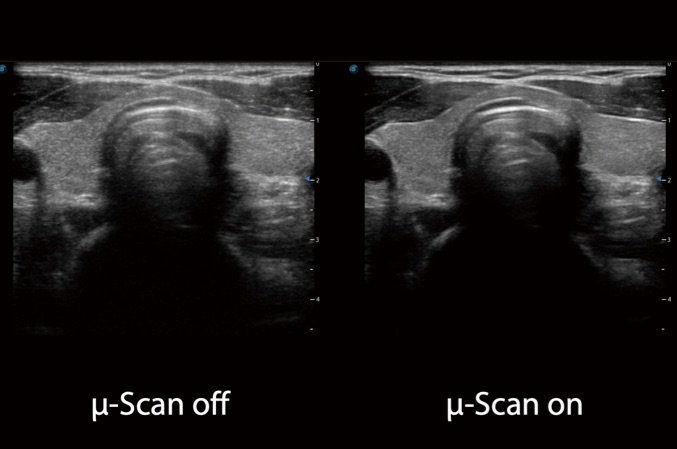

微米成像技术大大提高了器官和病变的可见性。高清对比度分辨率将抑制斑点噪声,同时保持真实的组织结构。